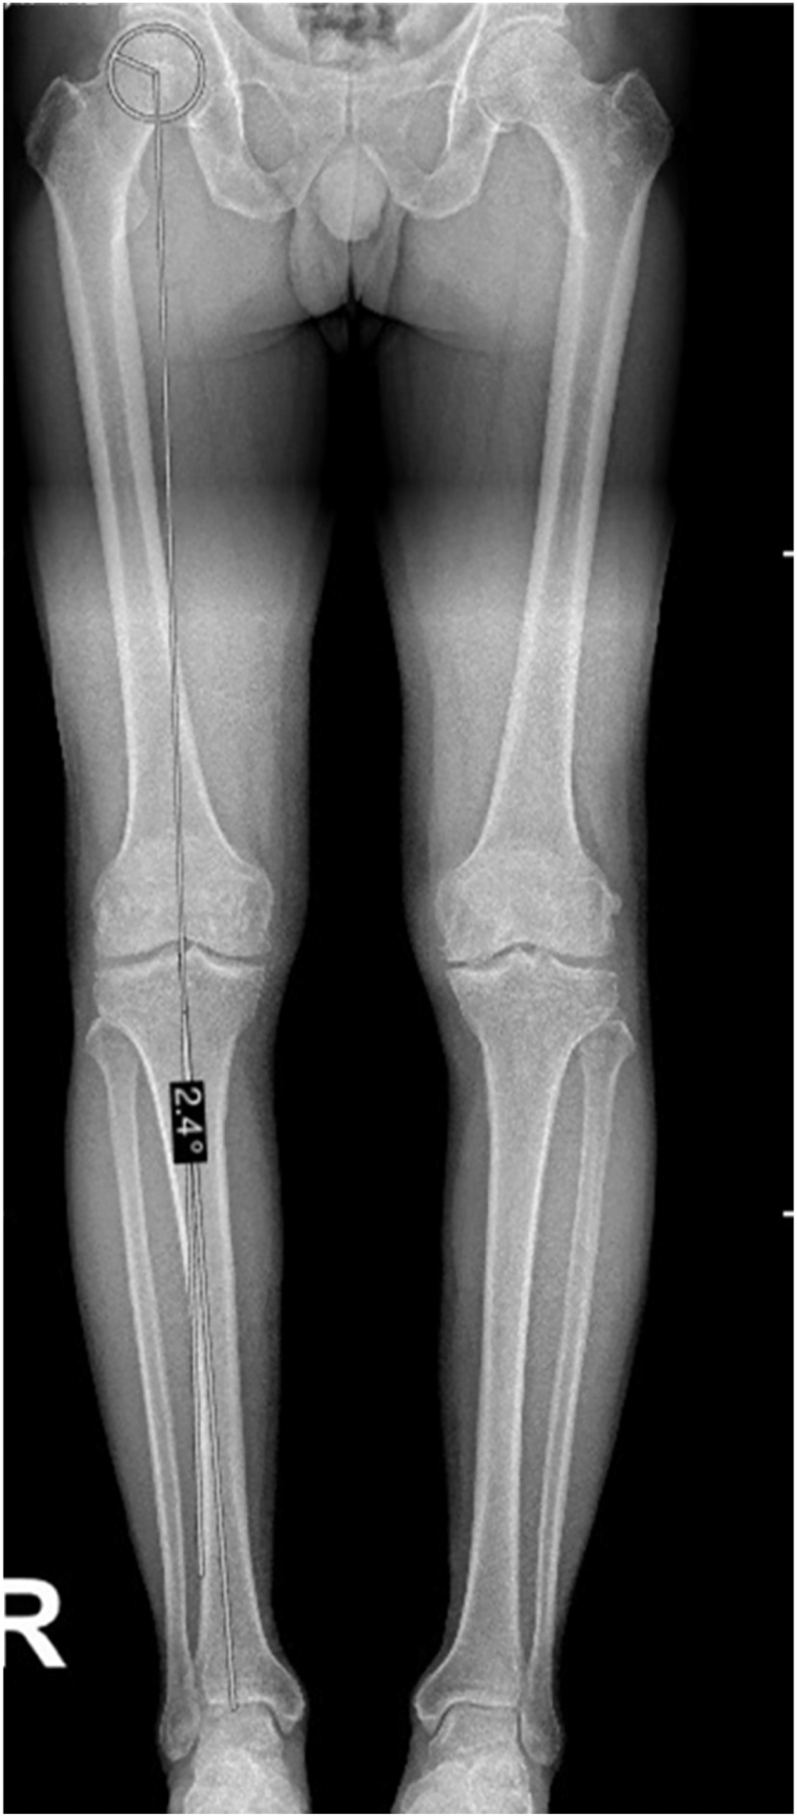

This review presents a standardized, stepwise method for biplanar radiographic analysis of knee alignment, integrating both coronal and sagittal measurements for use in arthritic and non-arthritic knees. It critically compares leading classification systems, including the coronal plane alignment of the knee (CPAK) and the functional knee phenotype classifications. While CPAK provides a simplified 2D coronal model, the functional phenotype system offers a more granular, 3D approach that includes segmental deformities and has recently been expanded to incorporate laxity parameters. Sagittal plane parameters - including posterior tibial slope and femoral component flexion/extension - are essential for comprehensive alignment assessment. These factors influence implant positioning, knee kinematics, and postoperative function. The review outlines preferred measurement techniques, highlighting the value of long-leg weight-bearing radiographs and discussing the limitations and variability of 2D versus 3D imaging approaches. Incorporating both alignment and soft tissue behavior provides a more individualized approach to total knee arthroplasty planning and may lead to improved outcomes by better replicating native knee biomechanics.